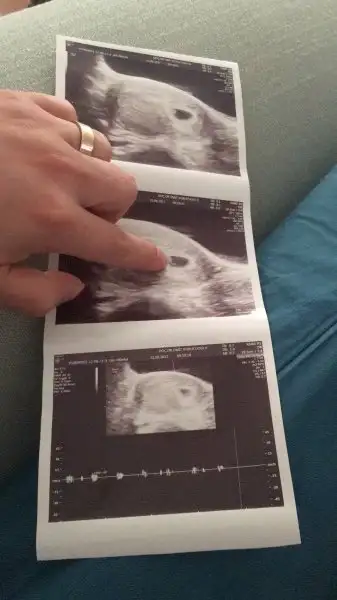

Bana da yorum lütfen?

20170814_080252.webp

Burda 9 haftalikti. Yorumlarsaniz cok seviniirm :)